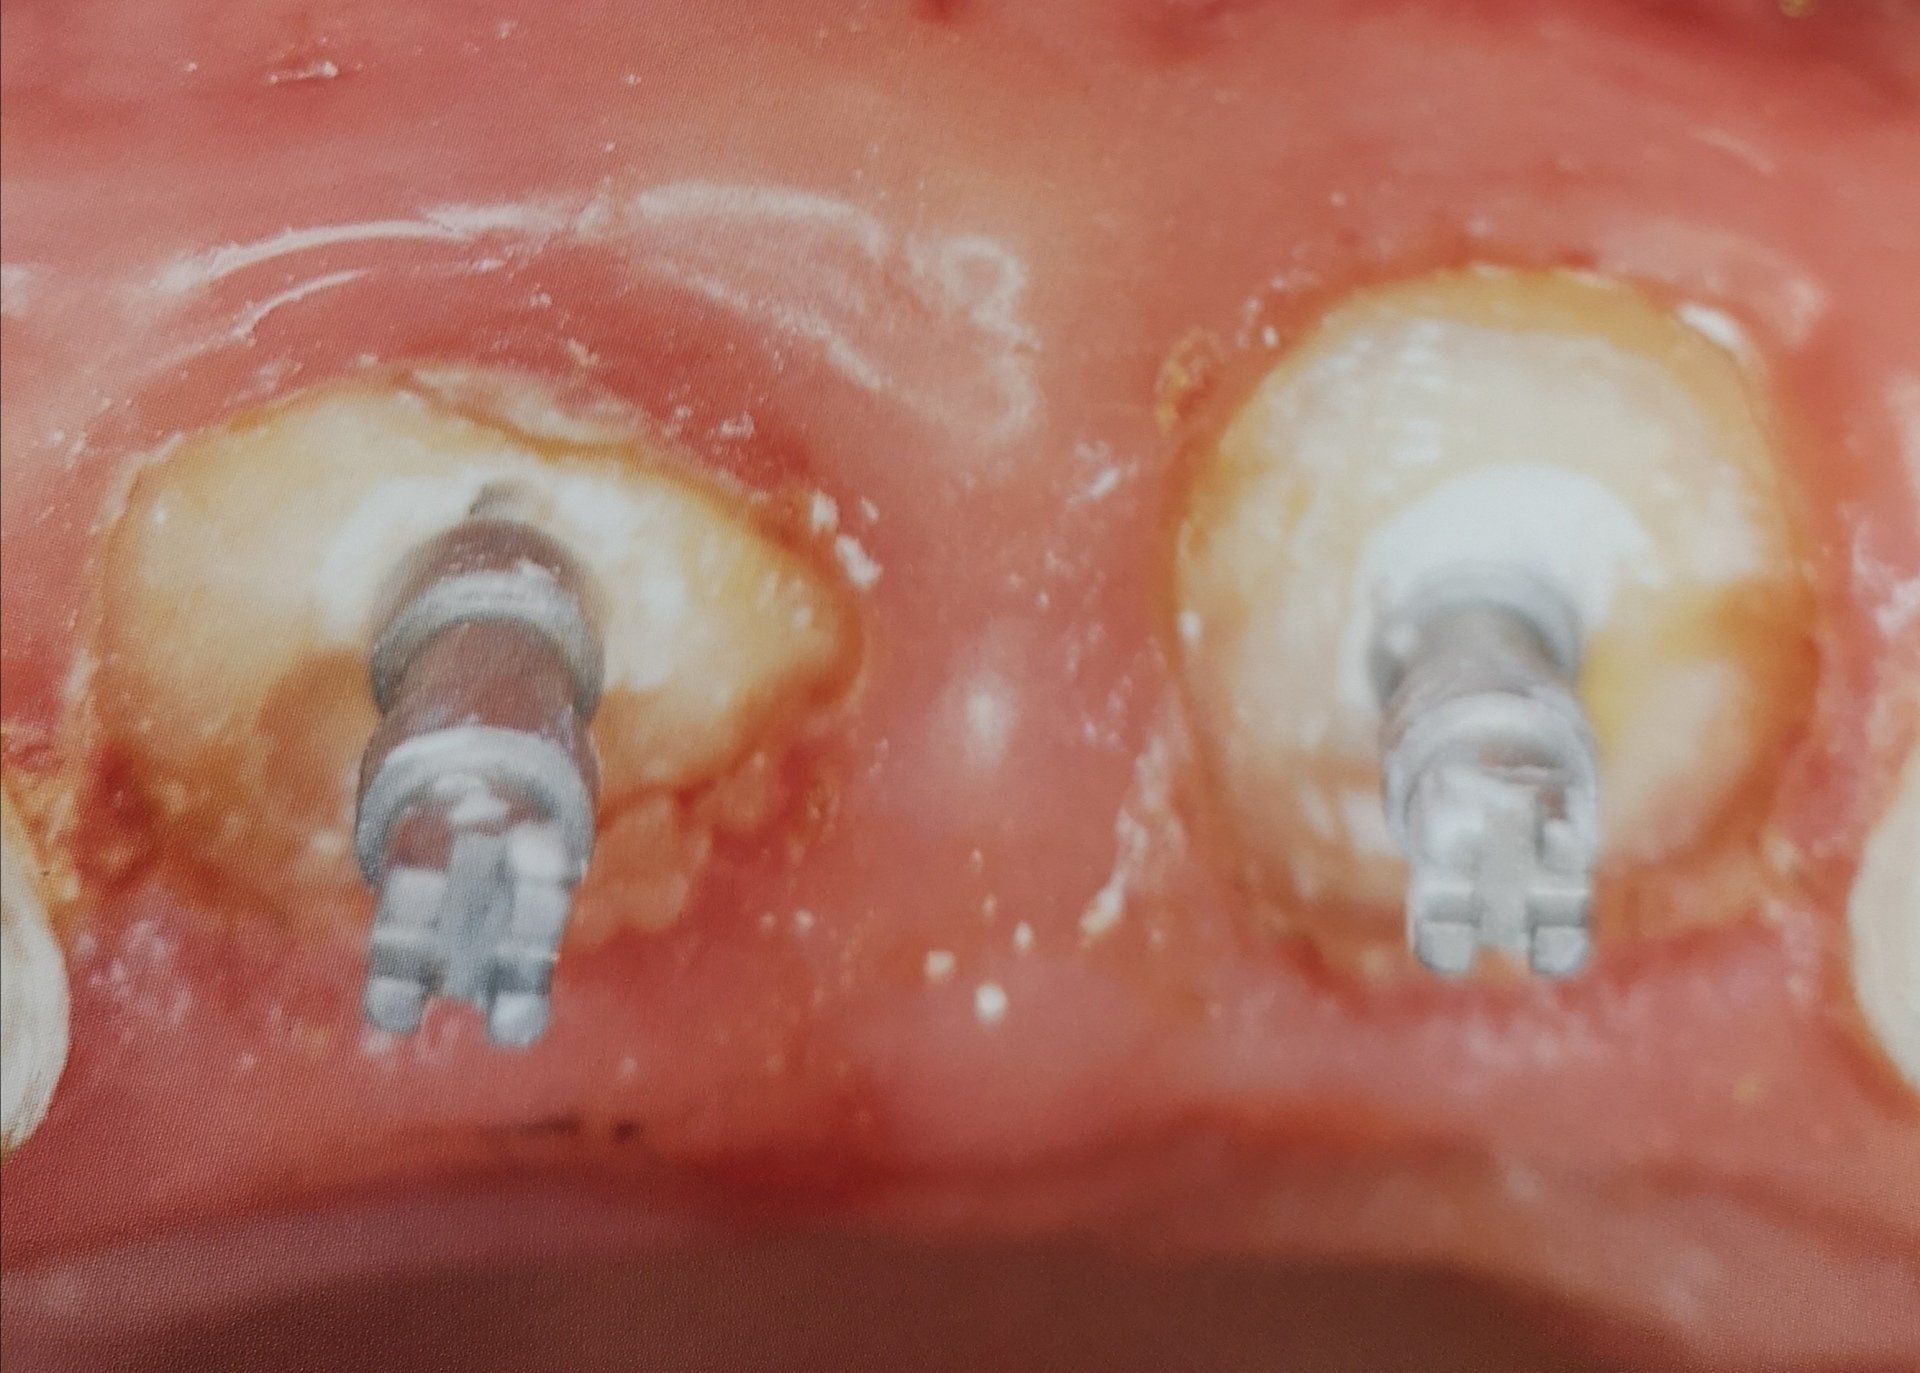

Grazie alle moderne tecnologie usate dalla dott.ssa Lombardi Paola Daniela, l’intervento è rapido, indolore e permette di salvare sia il dente naturale evitandone l’estrazione, che radici residue utilizzabili come pilastri per capsule.

La Dott.ssa Lombardi interviene rimuovendo il tessuto infetto, disinfettando accuratamente i canali radicolari e sigillandoli, permettendo così di salvare il dente naturale e di evitare l’estrazione.

In alcuni casi, la Dott.ssa Lombardi può consigliare di rinforzare il dente con una capsula o un intarsio, per aumentarne la resistenza nel tempo.

La Dott.ssa Lombardi utilizza inoltre tecniche di restauro diretto e indiretto (come intarsi o faccette), progettate digitalmente per garantire precisione e adattamento perfetto.